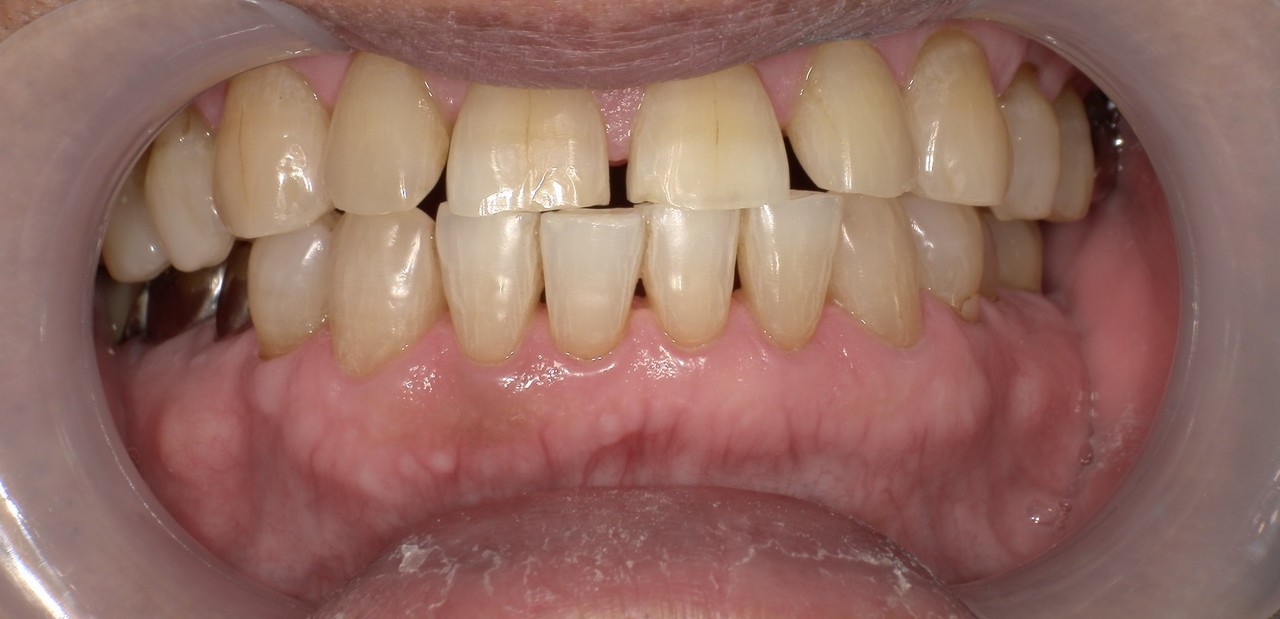

ステイン除去

BEFORE

AFTER

年齢:20代男性

治療内容:エアーフローによる歯の着色汚れ、ステイン除去

治療期間/通院回数:1回

費用: ステインコース 8,800円

リスク・副作用

①効果には個人差があり、着色汚れによっては一度に取りきれない場合があります。

施術後数時間以内に、着色効果の強いもの(コーヒー・紅茶・喫煙など)を摂取すると、歯に色素沈着が起こる可能性があります。

パウダーの刺激により歯ぐきから出血する可能性があります(痛みはほとんどありません)。